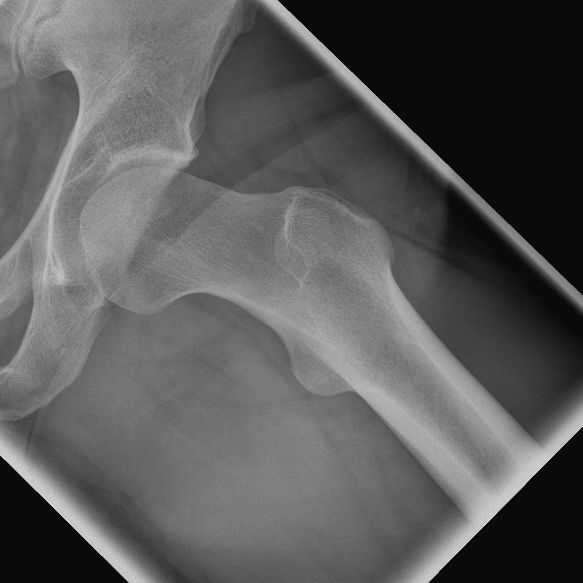

Ein stark vorstehender knöcherner Pfannenrand (Pincer- oder Beißzangen-Impingement) oder ein inhomogener knöcherner Übergang des Hüftkopfes in den Schenkelhals (sog. CAM- oder Nockenwellen-Impingement) liegt oft bei Hüfterkrankungen vor, die schon im Kindesalter beginnen. Allerdings treten die ersten Beschwerden häufig erst im Erwachsenenalter auf. Die Hüftarthroskopie bietet dabei die Möglichkeit einklemmende Knochenüberstände abzutragen und die Kontur des Hüftkopf-Schenkelhalsbereiches durch spezielle Fräsen wieder zu normalisieren. Dadurch wird ein vorzeitiger Hüftverschleiß verhindert.